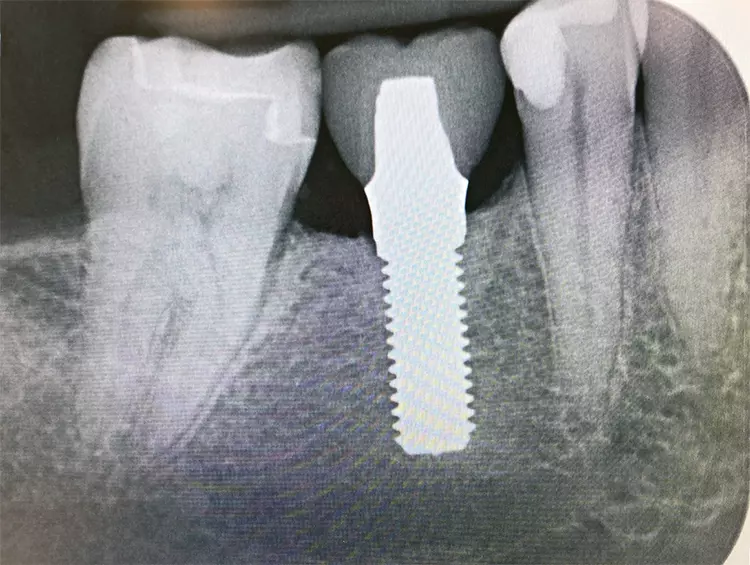

Das Patent™ Implantatsystem nimmt hier eine Vorreiterrolle ein: Dem Schweizer Innovationszentrum Zircon Medical Management ist es dank einzigartiger Designfaktoren, eines materialwissenschaftlichen Grundverständnisses sowie eines patentierten Herstellungsverfahrens gelungen, eine festere Weichgewebsanhaftung um Patent™ Implantate zu erzielen (Abb. 1). Dieser sogenannte „Soft-Tissue Seal“ verhindert das Eindringen pathogener Bakterien aus der Mundhöhle in das Körperinnere und biologische Komplikationen wie Periimplantitis, Perimukositis oder marginaler Knochenverlust können reduziert oder sogar verhindert werden.

Das Patent™ Implantatsystem bedient sich einer einzigartigen Kombination aus Design und Material, die es dem periimplantären Weichgewebe ermöglicht, weitgehend reizfrei und ungestört von bakteriellen Erregern, fest an seiner transgingivalen Tulpe zu haften und eine Manschette zu bilden. Der transgingivale Anteil des Patent™ Implantats bietet ideale Oberflächeneigenschaften für die Anhaftung von Weichgewebe, da er maschiniert ist und im Gegensatz zu seinem hochrauen enossalen Anteil nach dem Fräsen keine weitere Oberflächenbehandlung erfährt.

Darüber hinaus wurde das Patent™ Implantat mit einem Soft-Tissue-Level-Design entworfen, um die Gefahr eines bakterienanfälligen subgingivalen Mikrospalts, der sich nachweislich negativ auf die Hart- und Weichgewebsintegrität auswirken würde, zu vermeiden [1-4]. Die Implantatplatzierung auf Gingivaniveau positioniert die Implantat-Abutment-Grenze äquigingival und somit in einem kontrollierbaren und mundhygienisch pflegbaren Bereich. Nicht zuletzt ist auch das Implantatmaterial für die unschlagbare Weichgewebsintegration des Patent™ Implantats entscheidend: Das für die Herstellung verwendete Yttrium-stabilisierte Zirkoniumdioxid hat sich aufgrund seiner besonderen Gewebefreundlichkeit und hohen Bruchfestigkeit als Goldstandard unter allen verfügbaren Implantatkeramiken etabliert.